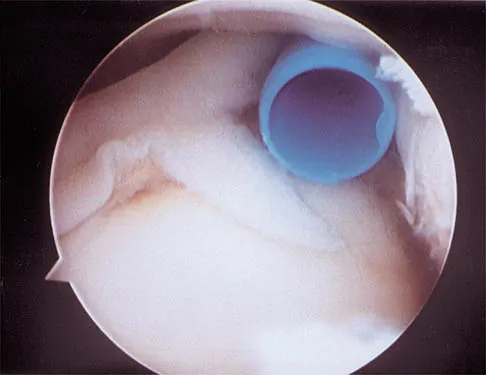

A 24-year-old athlete has a painful right shoulder. Figure 30 shows an intra-articular photograph that was obtained through a posterior portal during arthroscopy; the labrum is indicated by the arrow. Based on these findings, management should consist of

Explanation